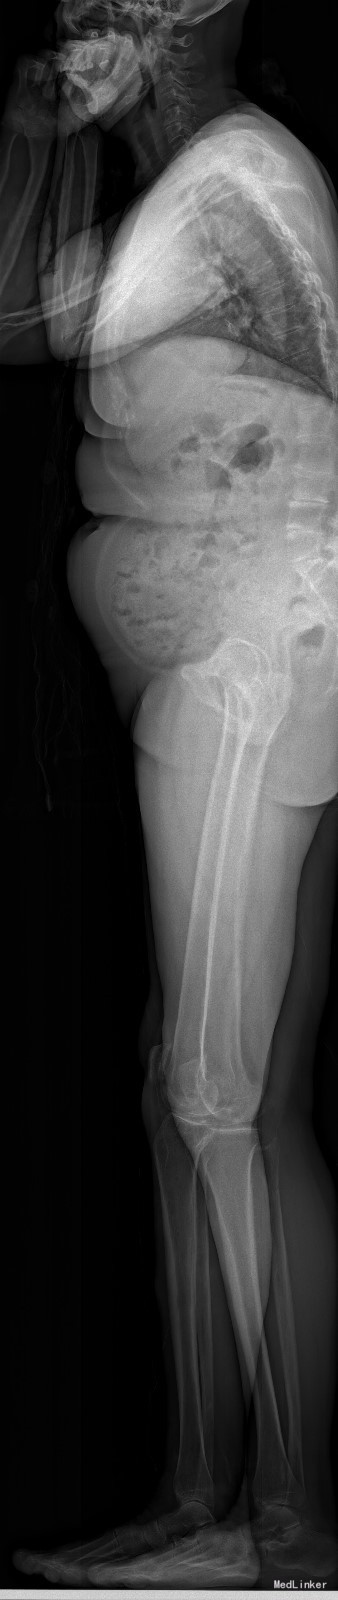

查体:脊柱无明显侧弯,腰背部无压痛,双下肢麻木酸痛,可牵连至脚跟。肌力肌张力可。腰部活动可,前屈后伸时感酸痛,无力。左侧直腿抬高试验阳性。 辅助检查:X线平片:腰椎侧弯前屈,L3椎体轻度滑脱,各椎间隙狭窄,腰椎退行性改变。 MRI:L4-5,L5-S1椎间盘膨出,L2-3,L3-4,L5-S1椎间隙狭窄,S2-3水平骶管内蛛网膜囊肿,腰椎序列不稳定,生理曲度局部后凸。

诊断:1 脊柱侧弯 伴不稳 2椎管狭窄 治疗: 前期微创腰椎侧路融合手术+后期 微创后路经皮内固定